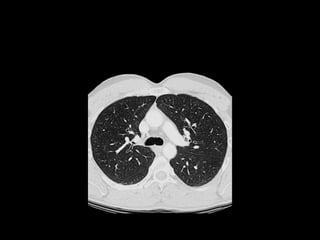

The document discusses the anatomy of the chest x-ray and CT scan by describing the lobes of the lungs and their locations. It also mentions the heart, mediastinum, hilum, and ribs. Several axial, coronal, and sagittal CT images are included with labels pointing out structures like the trachea, bronchi, lobes of the lungs, and fissures. In summary, the document provides an overview of lung and chest anatomy as seen on x-rays and CT scans through text descriptions and labeled medical images.